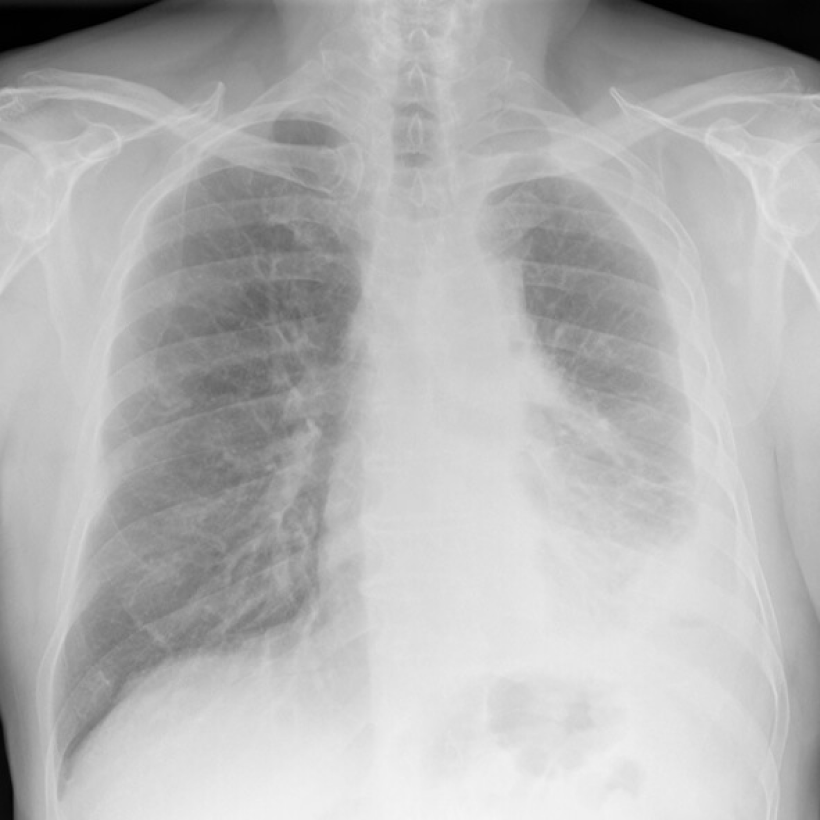

What Does Mesothelioma Look Like on an X-Ray?

Digital chest x-ray of advanced malignant mesothelioma on left.

Lighter and hazy areas on the X-ray show possible mesothelioma tumors.

On a chest X-ray, pleural or pericardial mesothelioma tumors appear as wispy white areas around the lungs, while calcified tumors appear bright white. Bones appear white and healthy lungs are dark. Most abnormalities appear as lighter areas that are hazy or solid.

Tumors and scarring may distort chest anatomy. Compressed lungs or a raised diaphragm can be visible on an X-ray.

X-rays are 2D, making it hard to determine if a tumor is in the lung, pleura or the mediastinum around the heart. Additionally, X-rays don’t clearly show peritoneal or testicular mesothelioma. CT, MRI and PET/CT scans offer more detailed images for all mesothelioma types.